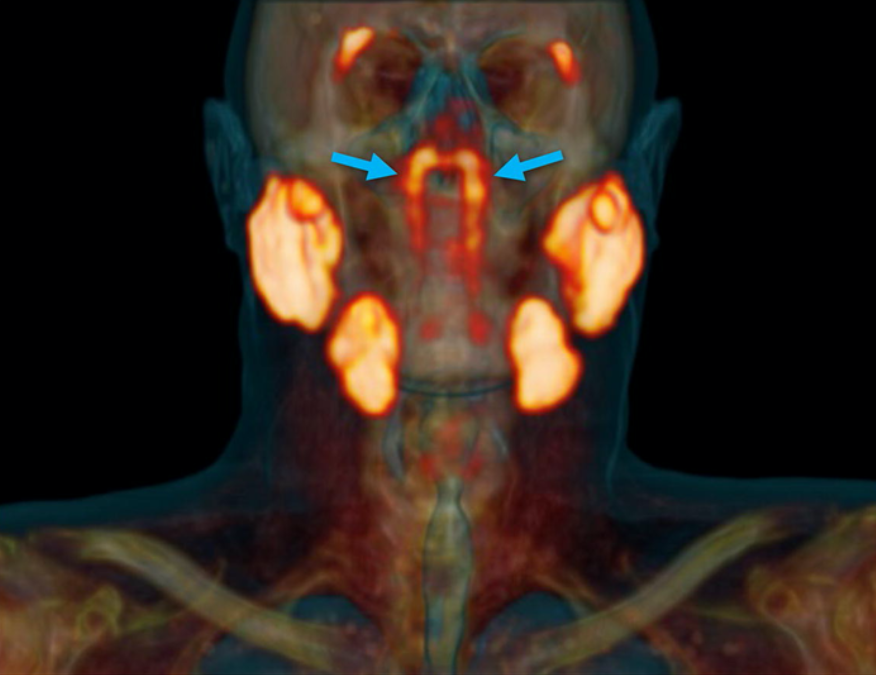

Новый орган был найден во время сканирования PSMA PET/CT. Обычно, в сочетании с инъекциями радиоактивной глюкозы этот диагностический инструмент выявляет опухоли в организме. В данном случае, однако, обнаружилось нечто совершенно иное, расположившееся в задней части носоглотки и довольно долгое время скрывавшееся.

На обнаруженные железы указывают синие стрелки (фото: Valstar et al., Radiotherapy and Oncology, 2020)

Новое открытие, сделанное командой Фогеля, показывает, что обнаруженные железы намного больше, чем те, которые можно увидеть только под микроскопом. Ученые предполагают, что это еще один набор основных слюнных желез.